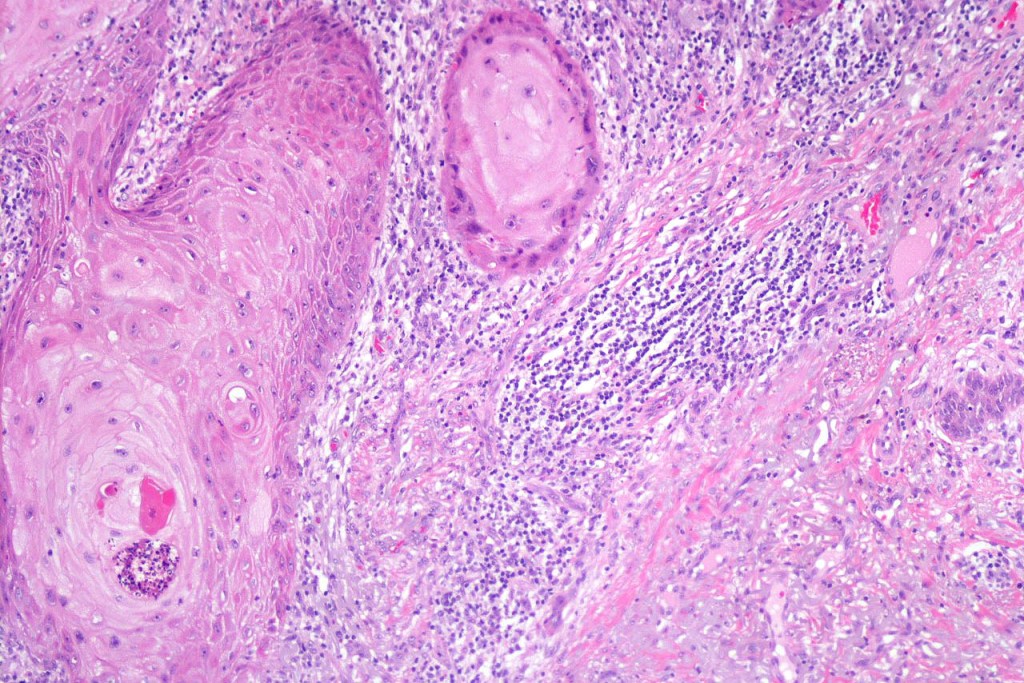

•Well differentiated squamous epithelium often with a characteristic ground-glass appearance

•Only mild pleomorphism & basally located mitoses

•Neutrophil-rich microabscesses & necrosis

•Entrapped elastic fibers undergoing transepidermal elimination

Below is a fascinating case shared on McKee Derm by Dr. James Simpson. There is an obvious keratoacanthoma but at the edge of the lesion there is marked atypia with nuclear enlargement and pleomorphism. This is also evident in the adjacent epidermis and in the deeper nests.